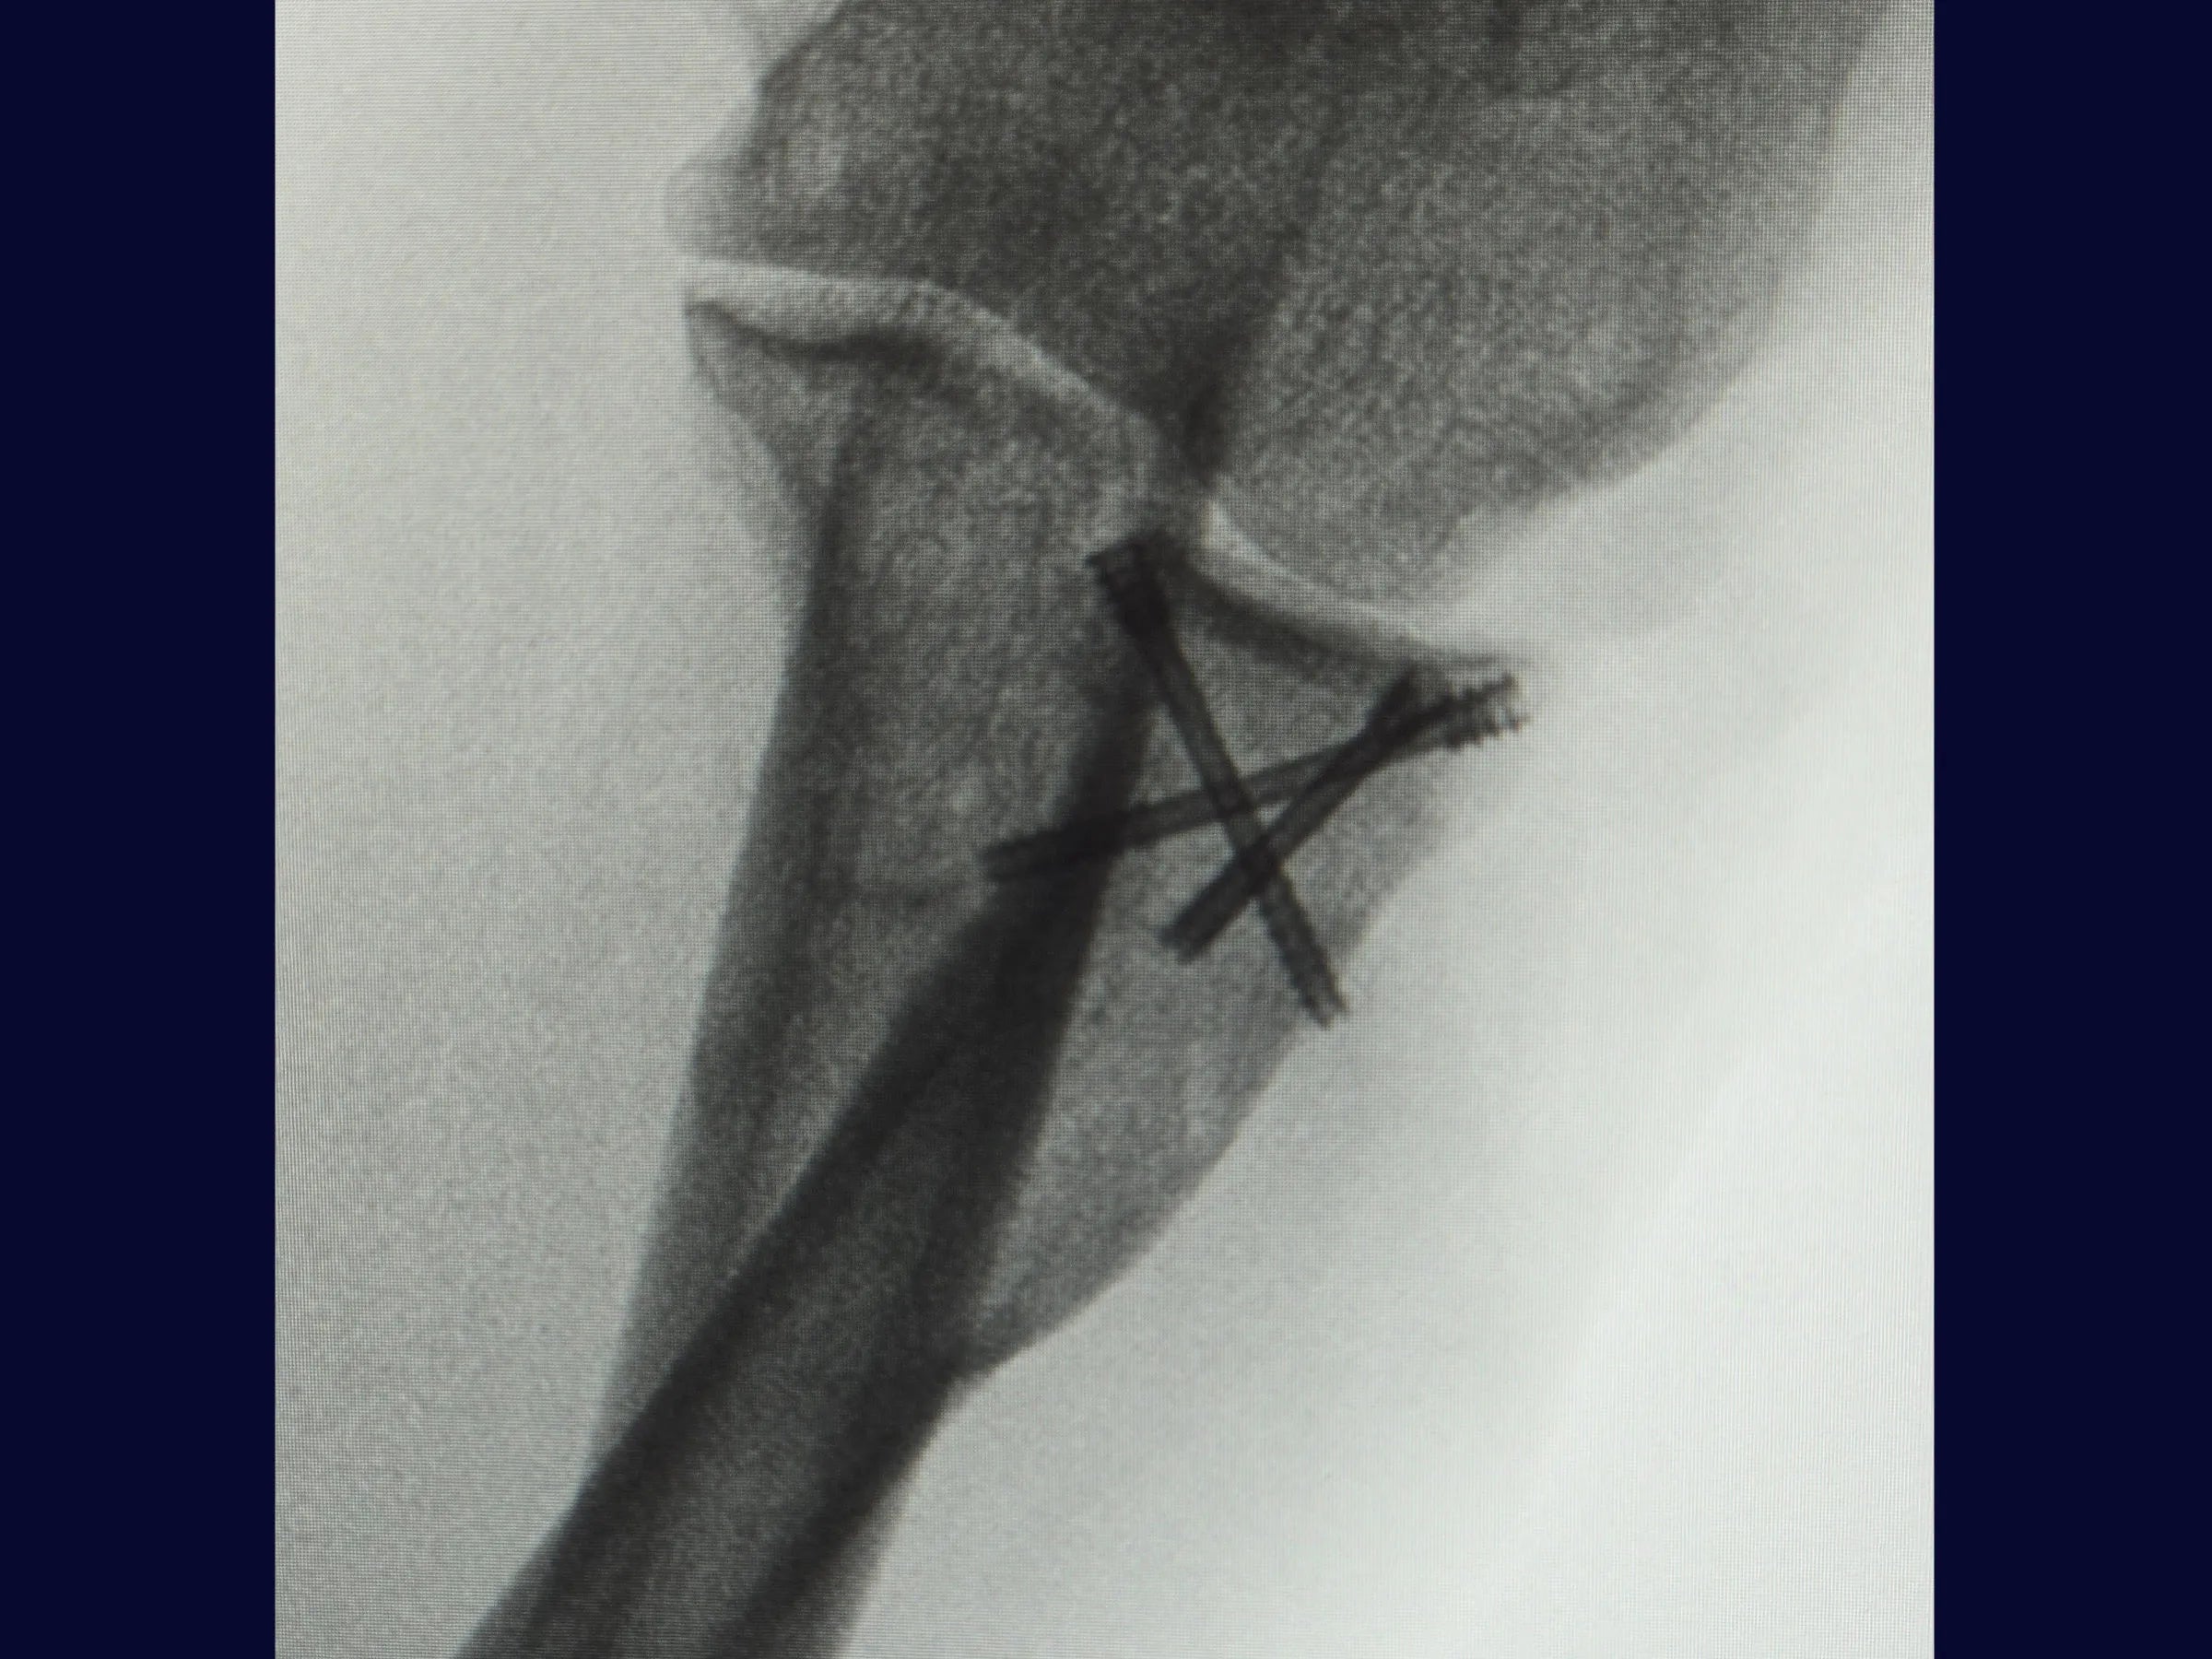

Este treinamento apresenta a técnica do tripé com parafusos de dupla compressão e reinserção capsular com âncora metálica, em vídeo 4K sob a perspectiva cirúrgica, permitindo compreender cada detalhe técnico e aplicar com segurança na prática.

- Técnica do tripé com parafusos de dupla compressão (2,4 mm).

- Fixação Segura: Parafusos sepultados em ângulo biomecânico de 45°.